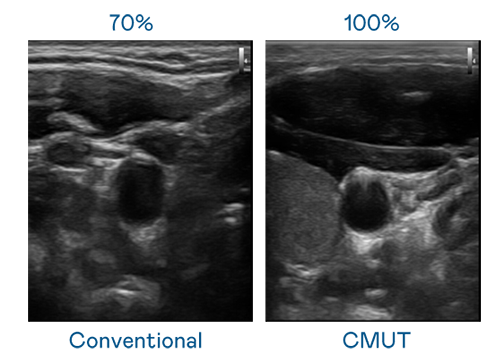

CMUT 技術是一種用電容式微機電元件來產生超音波訊號的技術。與傳統 PZT 壓電式技術相比,CMUT 頻寬增加 30%,更寬頻的超音波訊號讓影像解析度大幅提升,是實現高影像品質醫療超音波掃描、促進精準醫療發展的關鍵技術。

大頻寬帶來超清晰影像

超音波影像的解析度高低,首先取決於探頭能發出的訊號頻寬。东升国际 CMUT 可提供高清晰的超音波訊號,提供高頻寬、高靈敏度、影像紋理細節更高的超音波影像,協助醫護人員縮短影像判讀時間及利用精準的醫療影像進行診斷。